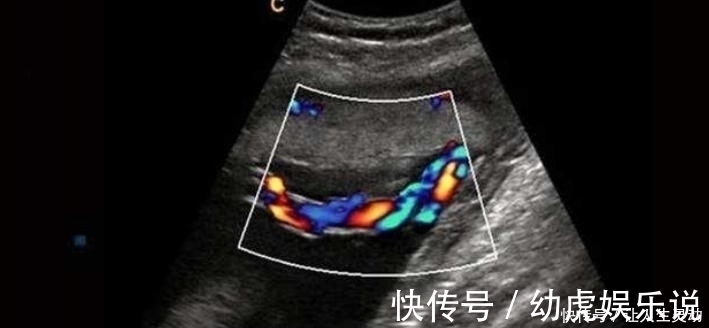

通过B超也能发现胎儿脐带扭转异常,从B超影像上能清晰地看见

文章插图

所以孕妈们一定要检查定期孕检,